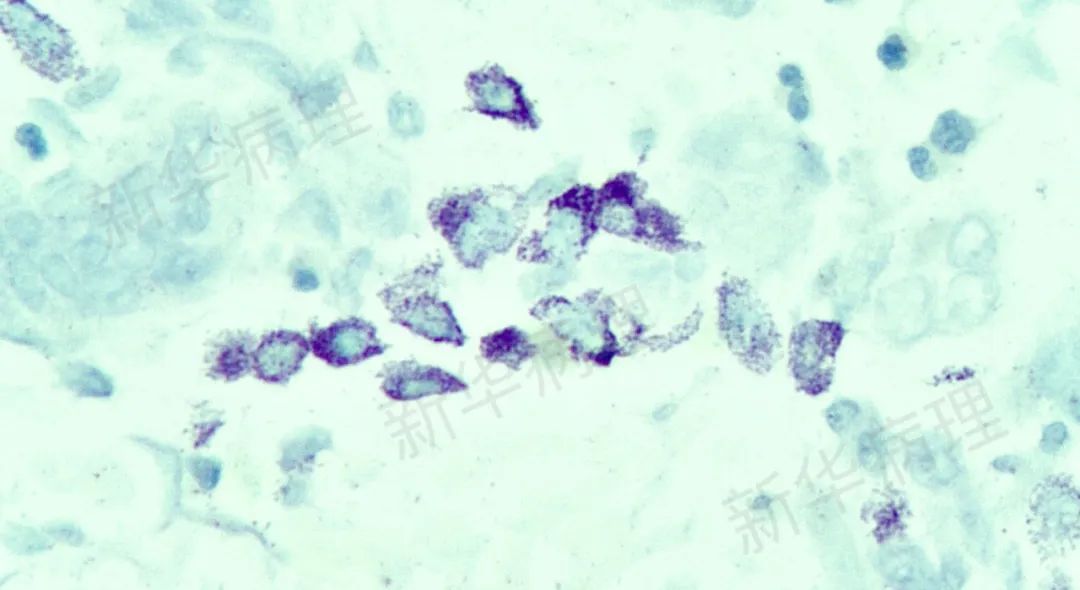

抗酸杆菌(Ziehl-Neelsen染色)